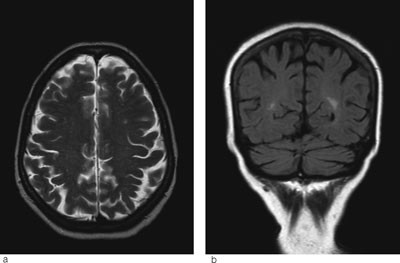

Senere samme dag ble det gjort MR-undersøkelse. Denne viste vasogent ødem parietooksipitalt, cerebellart og delvis i hjernestammen (fig 1a-d). Det var ingen tegn til infarkt eller sinusvenetrombose. Funnene var best forenlig med posterior reversibel encefalopati-syndrom (PRES). Pasienten ble overflyttet nevrologisk avdeling for videre behandling.

Ved MR cerebrum er det som regel karakteristiske funn ved posterior reversibel encefalopati-syndrom med vasogent ødem parietooksipitalt bilateralt (5). I uttalte tilfeller, som hos vår pasient, kan man se slike forandringer i hjernestammen og cerebellum, sjeldnere i fremre deler av cerebrum (6). T2-vektede MR-bilder og FLAIR-sekvenser er sensitive for ødem, som vises som høysignalforandringer (fig 1a-b).

Hjerneødem kan være cytotoksisk (cellulært) eller vasogent (interstitielt). Ofte foreligger det en kombinasjon. Ved hjerneinfarkt dominerer det cytotoksiske ødemet og celledød (fig 3a-b). Ved posterior reversibel encefalopati-syndrom får man et vasogent ødem som i utgangspunktet er reversibelt, men som uten behandling kan utvikles til cytotoksisk ødem og gi permanent cellulær skade. Ved hjelp av MR med diffusjonsvekting (DWI) og ADC-kart kan man skille mellom cytotoksisk og vasogent ødem. Ved MR med diffusjonsvekting er det høyt signal ved cytotoksisk ødem, mens det vanligvis er lavt signal eller ingen signalendringer ved vasogent ødem. I noen tilfeller får man likevel høyt signal ved posterior reversibel encefalopati-syndrom. Dette skyldes at DWI-resultatet er satt sammen av bidrag fra både T2-vekting og diffusjonsvekting. Høyt signal på T2 kan derfor skinne igjennom til diffusjonsbildet. Dette var også tilfellet hos vår pasient (fig 1c). Det er derfor viktig med ADC-kart, hvor bidraget fra T2 er fjernet og man får et rent diffusjonsbilde (7). ADC-kart viser alltid lavt signal ved cytotoksisk ødem og høyt signal ved vasogent ødem, som ved posterior reversibel encefalopati-syndrom (fig 1d).